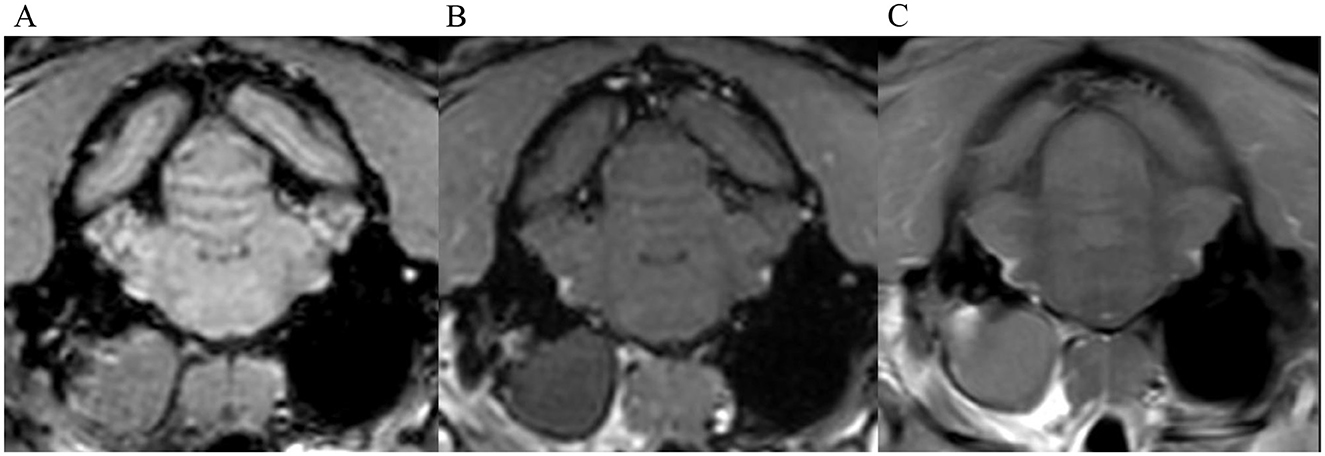

Figure 5. Transverse images at the level of the tympanic bullae. Example of a case where no inter-observer agreement was reached. (A) is the T1W-pre-contrast image. 1 of 5 observers did not interpret the 3D-GRE-T1W (B) as positive for meningeal enhancement but did interpret the FS-TSE-T1W sequence (C) as positive. No other observer detected meningeal enhancement in this case of a dog.

Figure 6. Transverse images at the level just caudal to the temporomandibular joints.Example of a case with marked meningeal enhancement and meningeal splitting in a cat. (A) is the T1W-pre-contrast image, (B) the 3D-GRE-T1W and (C) the FS-TSE-T1W.